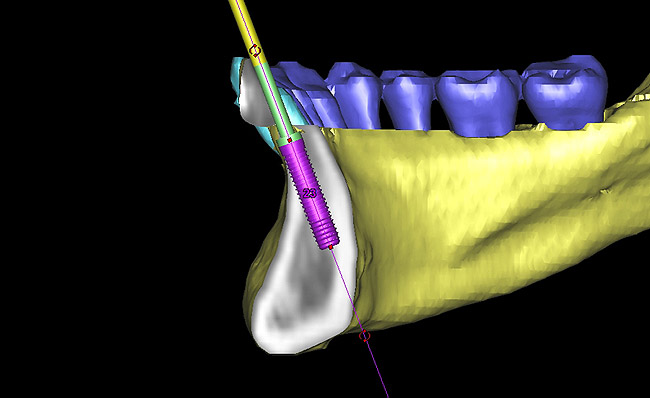

Figure 15  Presurgical 3-dimensional CT scan diagnostic planning for implant No. 23. Note the anticipated dehiscence at the facial aspect of the implant.

Figure 15

Figure 16  A cross-sectional view of postorthodontic site development at No. 23 position. Sufficient bone has been developed to accommodate implant placement in an optimal prosthetic position. Simultaneous GBR is planned at the coronal-most portion of the implant per anticipated dehiscence.

Figure 16